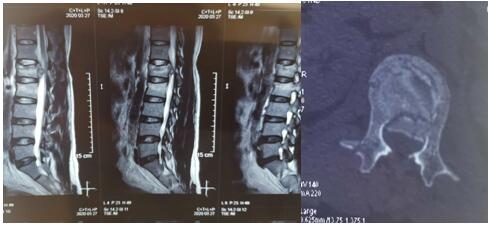

2020年3月26日夜,我院骨科二病區收住1例高處墜落傷致腰椎爆裂性骨折伴脊髓圓錐損傷、骨盆骨折、失血性休克合并右下肢深靜脈血栓形成患者,曹某,男性,42歲。查體:腰段及骨盆處壓痛,骨盆分離與擠壓試驗陽性,鞍區感覺減退。急診行MRI示:腰1椎體爆裂性骨折、腰2椎體壓縮性骨折,脊髓損傷;X線、CT+三維重建示:復雜骨盆骨折?;颊呦等矶嗵?、多發復雜骨折,病情危重,手術風險及難度高??浦魅瓮鹾捷x博士組織科室骨干醫生與神經介入科醫生,經深入討論后制定了詳細、縝密、有序的綜合救治方案,征得家屬同意后,急診在局麻下行下腔靜脈濾網植入術,植入順利,遂急診在全麻下行腰1爆裂性骨折并脊髓圓錐損傷、腰2椎體壓縮性骨折切開復位、椎板切開減壓椎弓根螺釘內固定術,待病情穩定后再二期行骨盆骨折切開復位內固定術。

術前影像學資料如下: